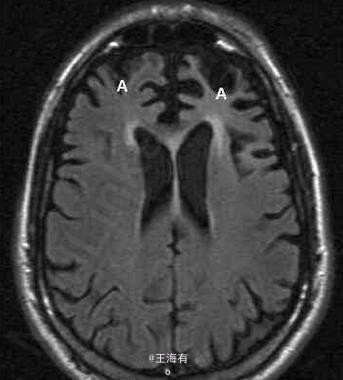

Pick病是一种罕见的进行性变性疾病,大多累及额叶和颞叶。预后本病预后不良。常在发病1年内迅速转入痴呆